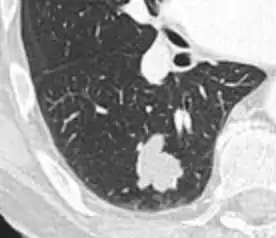

Lobulated nodule.[9]

Spiculated lung nodule.[9]